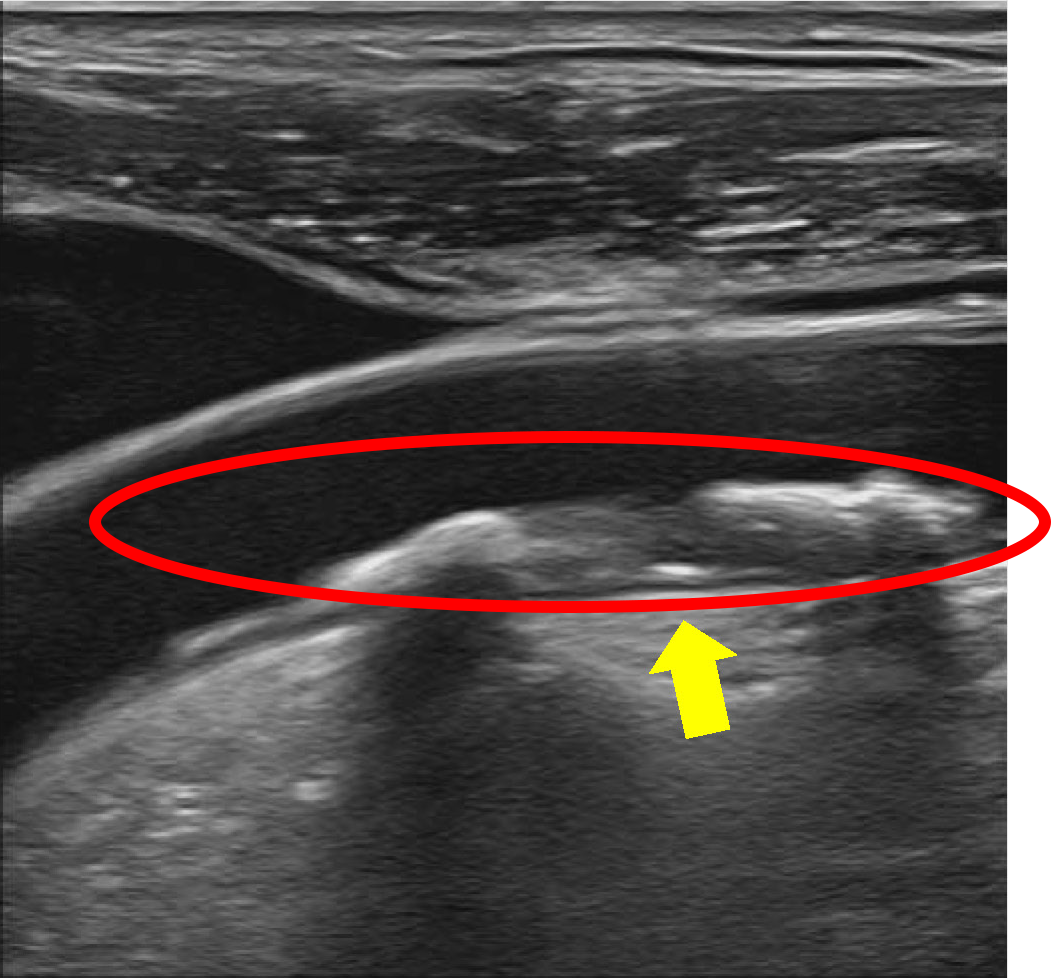

頸動脈エコー検査での1例

頸動脈エコー検査とは、動脈硬化の進行具合を調べることが可能な検査です。

【正常ではない血管】

血管にプラーク(コレステロールの塊)などがあり、血管が狭窄している状態

動脈硬化とは、血管にプラーク(コレステロールの塊)などがたまり、血管が硬くなったり、狭くなったりして血流が悪くなる状態のことです。加齢による老化のほか、高血圧、糖尿病、脂質異常症、喫煙などの危険因子が重なると、発症しやすくなると言われており、進行すると、脳梗塞や心筋梗塞、狭心症などを引き起こしてしまう可能性があります。